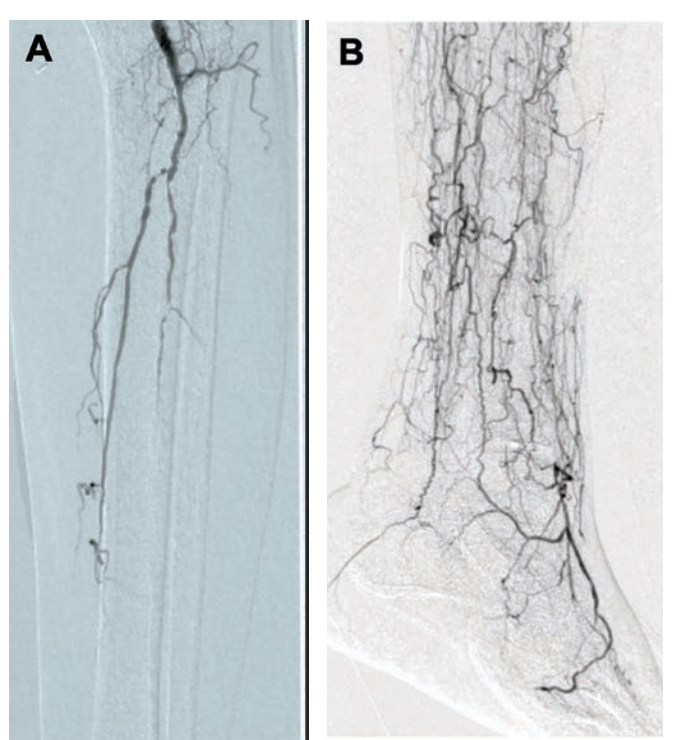

Revascularization was done with ZCT using CO2 angiography, extravascular ultrasound (EVUS), and intravascular ultrasound (IVUS) to preserve his residual renal function given his post-renal transplant CKD. EVUS-guided antegrade left common femoral artery (CFA) access was obtained with a 6F Destination sheath (Terumo) as well as left lateral plantar vein (LPV) access with a Micropuncture catheter (Cook). Baseline angiographic images were obtained with CO2 angiography using the CO2mmander Elite device (AngioAdvancements), injecting 10cc for every selective angiogram (Figure 2). Notably, there was a short segment of patent proximal DP without visualization of the distal DP or the patent plantar arch of the foot to adequately perfuse the forefoot and heal a transmetatarsal amputation (TMA) (Figure 2b). IVUS-guided orbital atherectomy (Philips Eagle Eye Platinum ST) of the POP, TPT, and proximal posterior tibial artery (PTA) with a 1.5 Classic Diamondback catheter (Abbott) was performed. Thereafter, we performed IVUS-guided balloonangioplasty of the distal POP with a 5- x 80-mm Ultraverse balloon (BD) and balloon angioplasty of the TPT and PTA with a 4- x 120-mm Ultraverse balloon.

Valvulotomy in the LPV was performed with a 4- x 120-mm UltraScore scoring balloon (BD). A 5- x 250-mm Viabahn covered stent (Gore) was placed across the fistula and down the PTV to the LPV. The Viabahn covered stent in the PTV was post-dilated with a 5- x 100-mm Ultraverse balloon, and the short segment in the PTA was post-dilated with a 4- x 40-mm Ultraverse balloon. The final angiography was performed with CO2 showing excellent blood flow to the foot (Figure 4). Hemostasis of the LPV access was achieved with a combination of an intravascular balloon endoclamp and external manual compression. Hemostasis of the left CFA was achieved with a Perclose Proglide closure device (Abbott).